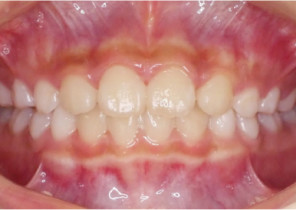

Post Invisalign Palatal Expander Expansion

After Invisalign First treatment

Pre Invisalign Palatal Expander Expansion